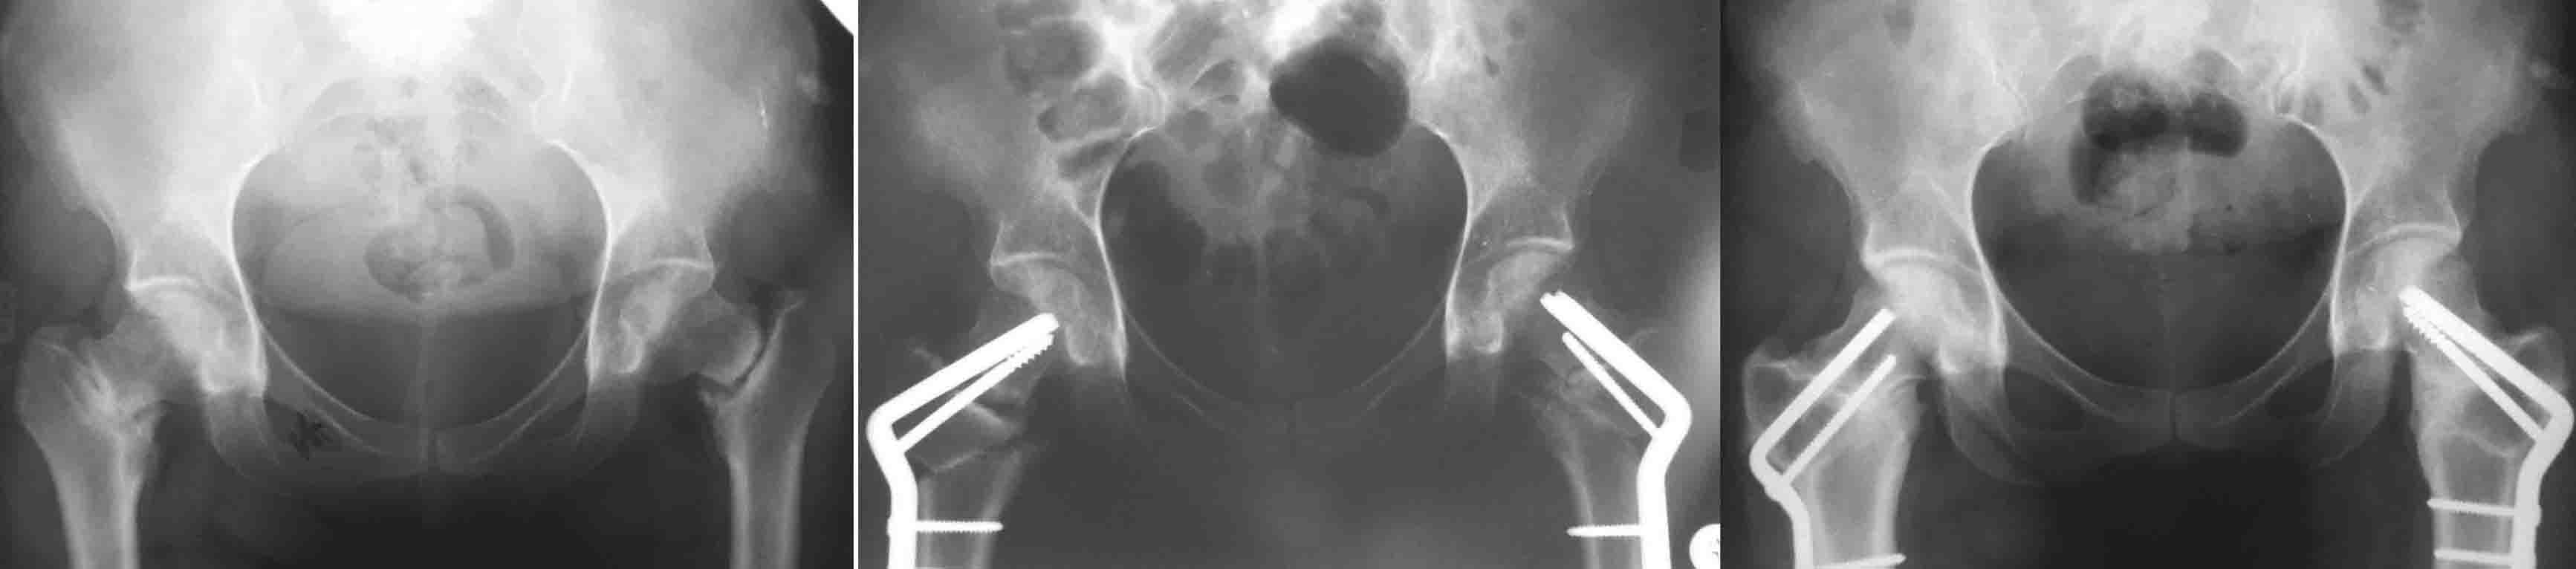

И клинковые и DHS, это всего лишь способ остеосинтеза, хотя, наверное, клинковые дают большую ротационную стабильность (по оси шейки), менее травматичны. Но это не постулат (1943 J Bone Joint Surg Am.;25:319-339. W. P. Blount BLADE-PLATE INTERNAL FIXATION FOR HIGH FEMORAL OSTEOTUMIES). При подвертельных остеотомиях с латерализацией клинковые пластины метод выбора (по другому латерализацию дистального не выполнишь). Оптимальними являються рассчеты СORA по Dror Paley (centr rotation and angulation). Взяты из книги Principles of Deformity Correction by Dror Paley. Для примера межвертельные при двусторонних ложных cуставах шеек.

Нет я имел в виду латерализацию.На приложенных снимках межвертельная остеотомия, т.е. уровень остеотомии близок к CORA, и ангуляция без трансляции (смещении по ширине латерализации) допустима: не будет происходить нарушение механической оси. В случае когда значительно укорочена шейка, большая разница в длине конечности и большая степень коррекции предпочтительнее подвертельная с латерализацией дистального фрагмента: функционально удлиняется шейка, большая коррекция длины конечности и нет натяжения m. Iliacus.